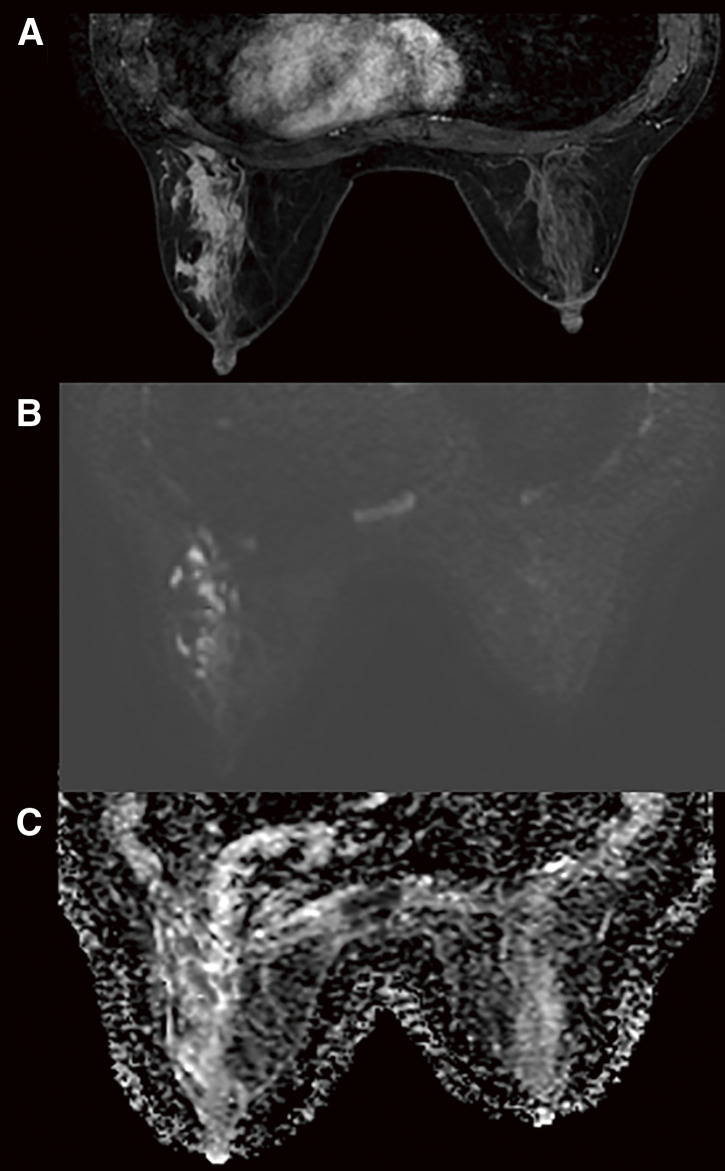

Case presentation: We report the case of a 36-year-old Japanese woman with granulomatous mastitis due to Mycobacteroides abscessus who had not undergone surgery and was not immunosuppressed. She presented with a chief complaint of pain and swelling in her left breast for 1 month. Mammography showed asymmetrical focal increased density, and ultrasonography showed an irregular hypoechoic area in the left 3 o'clock position. Contrast-enhanced magnetic resonance imaging showed segmental non-mass-enhancement. Ultrasound-guided vacuum-assisted biopsy with pathology revealed granulomatous mastitis. Ziehl-Neelsen staining revealed red-staining bacilli. The patient was followed up for observation because her breast pain had decreased after the examination, and there was no redness or fever. However, the breast pain has not completely disappeared, and intermittent purulent discharge from the biopsy site persisted for 5 months. Hence, two 12-Fr drains were inserted along the ductal dilatation-like hypoechoic area. Imipenem, amikacin, and clarithromycin were administered for 8 days. After 8 days of this therapy, the patient developed a drug-associated rash; therefore, antimicrobial therapy was discontinued, and the drains were removed. Her symptoms improved, and magnetic resonance imaging after 1 month showed that the previous imaging findings in her left breast had disappeared. At the time of writing, 18 months have passed since treatment, and no recurrence has been observed.